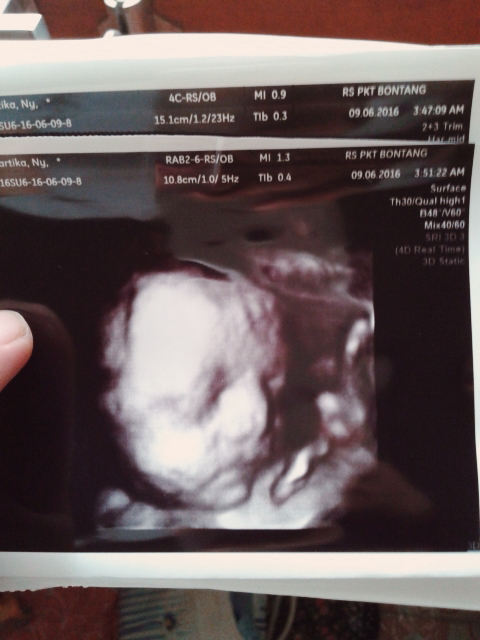

Первый триместр: Скрининговая программа и её важность